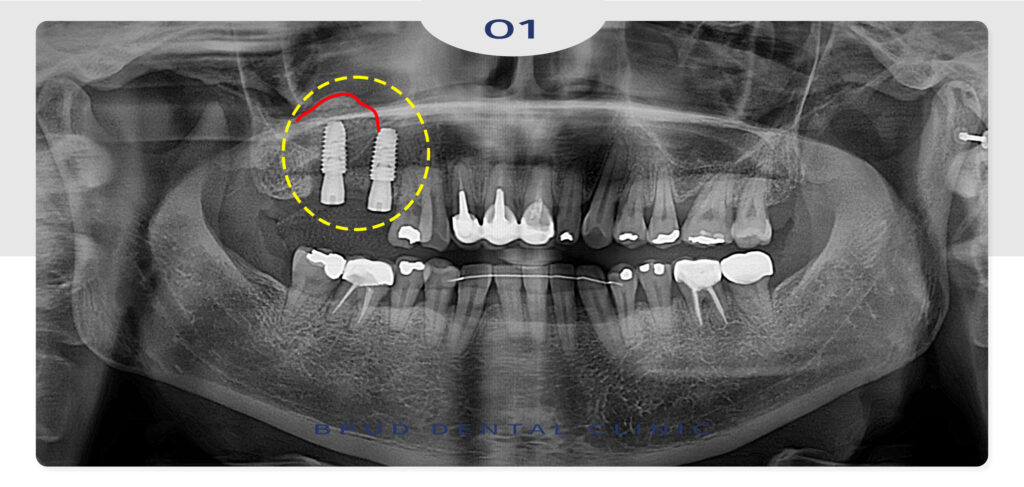

24.04.04

상악동 거상술은 측방 접근법과 치조정 접근법으로

나누어지는데 뼈 부족이 심한 경우는 잇몸을 절개한 후

상악동 측면에 작은 창을 내고 막을 들어올려 뼈이식재를

넣는 측방 접근법을 시행하게 됩니다.

또 뼈가 일부 부족한 경우에는 임플란트 삽입 위치를 통해

상악동을 직접 들어올리고 이식재를 채우는

치조정 접근법을 사용하는데 이는 비교적 간단한 방식으로

환자분의 부담이 적습니다.

위 환자분께서는 측방 접근법을 시행하였습니다.